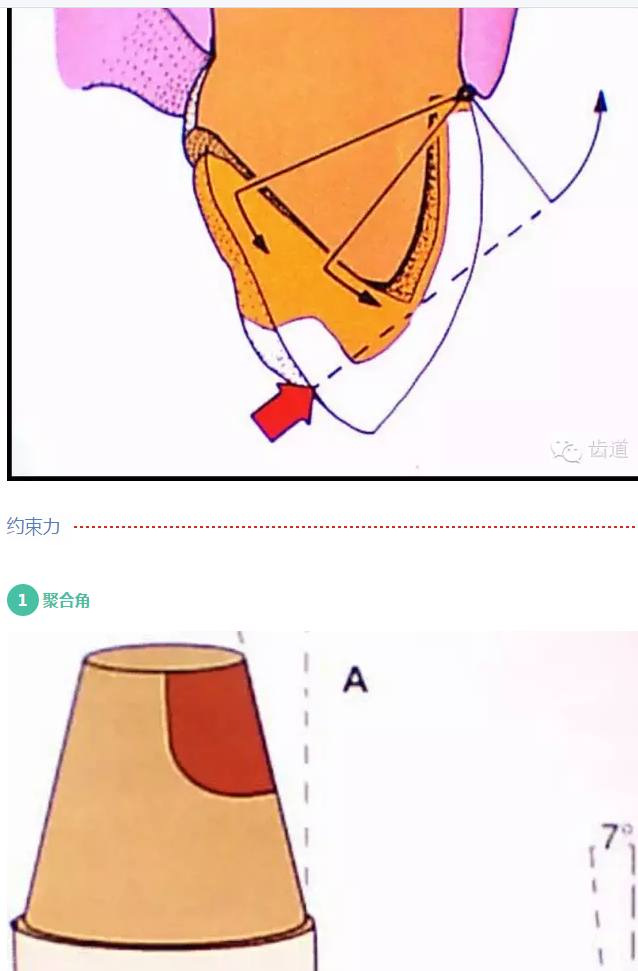

l基牙具有良好的固位形

l基牙具有良好的抗力形

牙的外形及洞形的幾何形狀:主要是牙體制備出一定聚合角度產(chǎn)生的阻擋作用